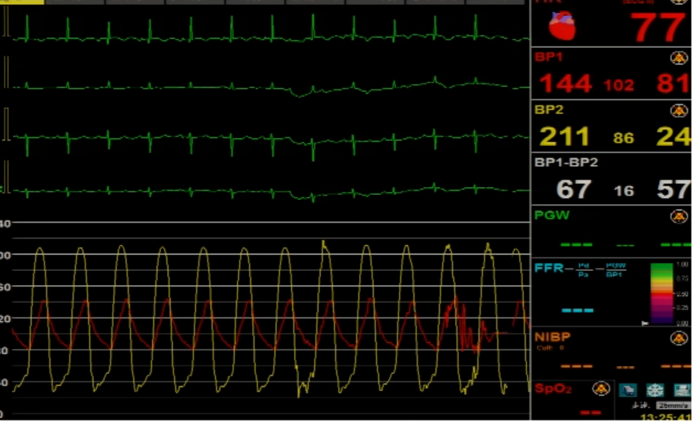

植入前后跨瓣压差

植入前压差67mmHg,植入后压差2mmHg